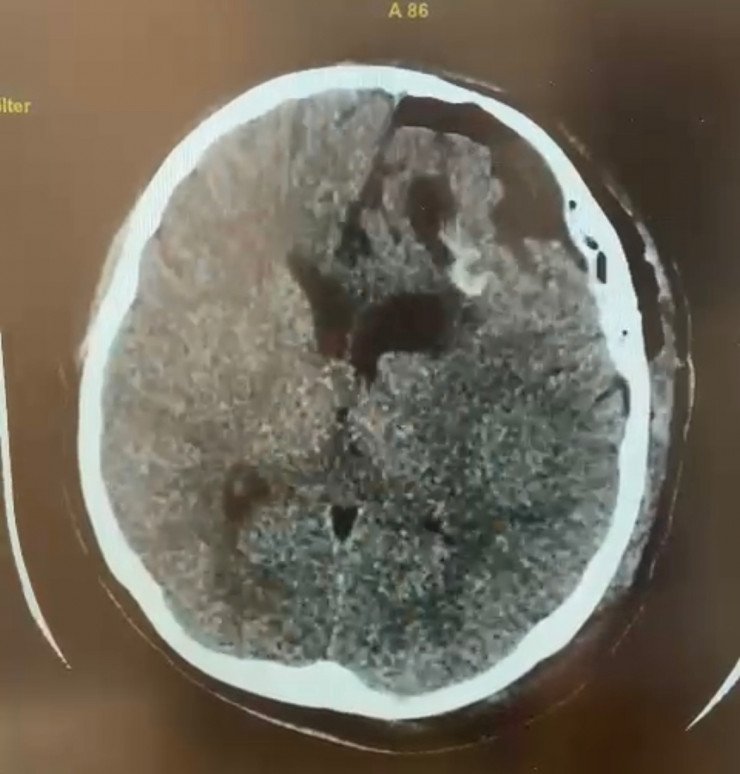

Накануне нейрохирурги Семея извлекли гигантскую эхинококковую кисту из головы пациентки. 20-летняя девушка поступила 17 января к невропатологам больницы скорой медицинской помощи (БСМП) Семея. Сначала у нее подозревали инсульт, однако на компьютерной томографии в головном мозге была выявлена огромная киста диаметром 5,5 сантиметра.

За короткое время был установлен диагноз "эхинококкоз" и принято решение о трепанации черепа и извлечении опухоли. Незамедлительно она была прооперирована.

КТ-снимок до операции.